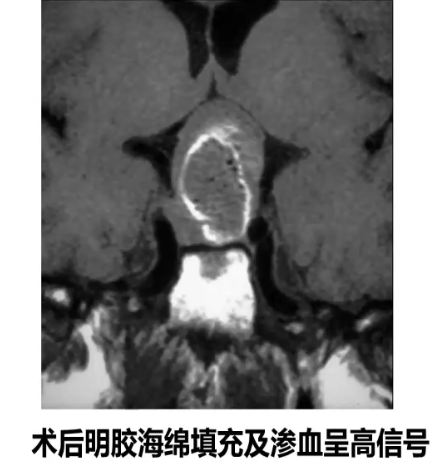

3、手术后高信号:手术填充材料(明胶海绵、脂肪);海绵窦受压血流减慢;手术区组织致密;残存垂体前叶激素分泌旺盛